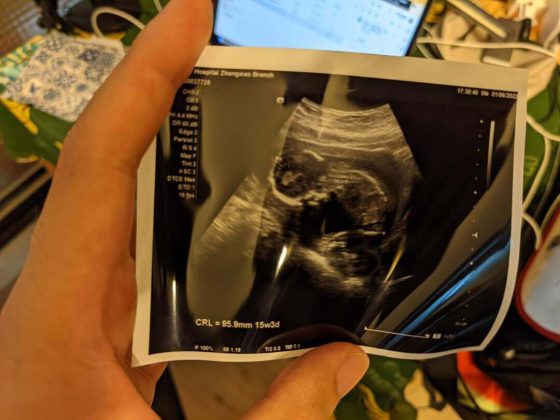

我是在太太孕期間讀完《超級嬰兒通》的,

書中有許多實用育兒觀念,幫助我在準爸爸時期,

對孩子出生後的生活有了更具體的想像與心理準備。